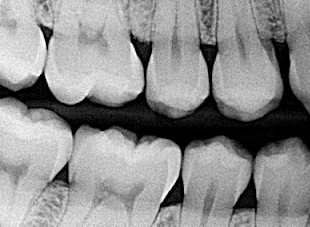

bitewing x-ray photograph X-Rays

Dental x-rays are special pictures taken of the insides of the teeth so that the dentist and hygienist may see if the person has cavities between the teeth. It is very important to get these pictures taken regularly because the dentist cannot see the sides of the teeth that touch. If a cavity is between the teeth and an x-ray picture is not taken, the dentist will not know if the cavity is there and cannot treat the cavity and stop it from growing larger. If the cavity is left to grow, it can become very painful.